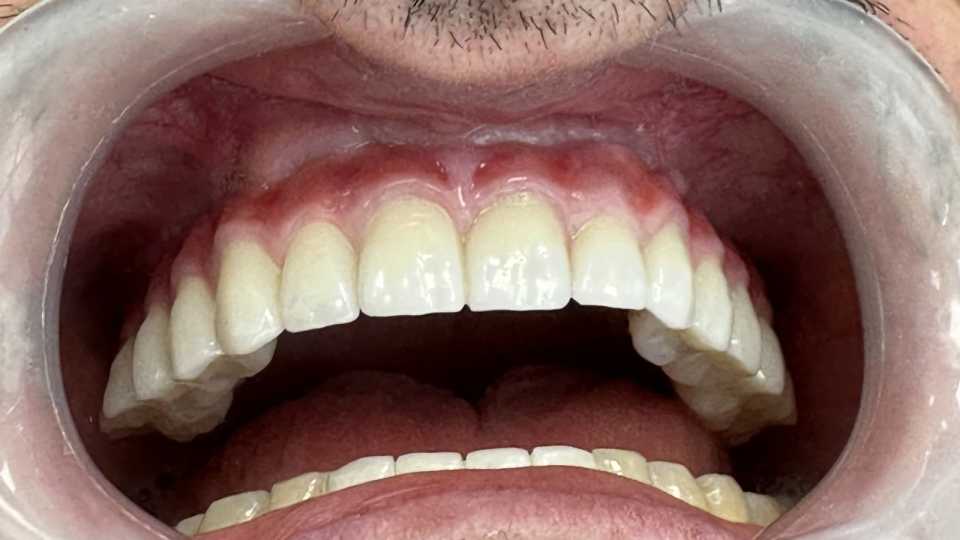

Pacient în vârstă de 39 de ani se prezintă în clinica noastră cu probleme de natură estetică și funcțională la nivelul maxilarului.

În urma consultului de specialitate, s-a decis extracția dinților parodontotici și a unei lucrări vechi, urmată de inserarea a 7 implanturi dentare Mega-Gen AnyRidge, cu adiții osoase și sinus lift bilateral. Implanturile au fost poziționate strategic pentru a permite o reabilitare protetică completă, formată din 14 dinți, asigurând astfel zâmbetul dorit de pacient.

Lucrarea protetică este fixă, înșurubabilă pe suport multiunit, realizată din ceramică pe suport de titan.